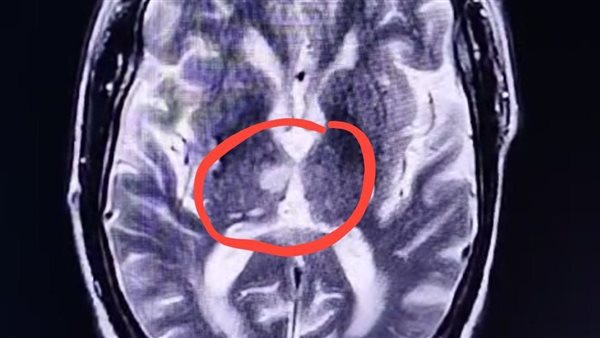

ومع استمرار غيبوبة المريض دون تفسير واضح، قرر الفريق الطبي، بقيادة الدكتور عمر جابر، طبيب مقيم بالعناية المركزة، والاستشاري الدكتور أحمد العربي، إجراء أشعة رنين مغناطيسي على المخ، ليتم اكتشاف المفاجأة الصادمة، جلطة دماغية أصابت منطقة تحت المهاد (Hypothalamic infarction)، وتحديدًا في مركز النوم بالمخ.

وأوضح الدكتور عبدالرحمن رجب، أن هذه الإصابة تعني أن المريض سيظل في حالة نوم عميق لفترة طويلة، وهي حالة نادرة للغاية، مشيرًا إلى أن تسجيل آخر حالة مماثلة في كينيا عام 2019.